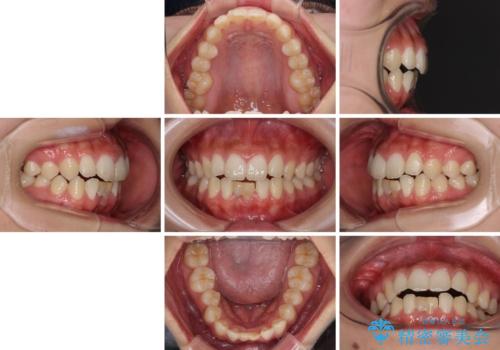

- 下顎前歯に乳歯が残っており、欠損もしていることを気にして来院された患者様です。

舌の突出癖が顕著にあり、上下前歯が非接触となっており、上顎前歯が前方に突出している状態でした。

マウスピースでもワイヤーでも対応可能でしたが、自己管理の煩わしさからマウスピース矯正は避けることとしました。

ワイヤー装置により矯正治療を行うとともに舌突出癖改善のためのトレーニングをしっかりと行っていただき、咬み合わせが安定した位置となったタイミングで下顎前歯にブリッジの仮歯を装着していく計画としました。